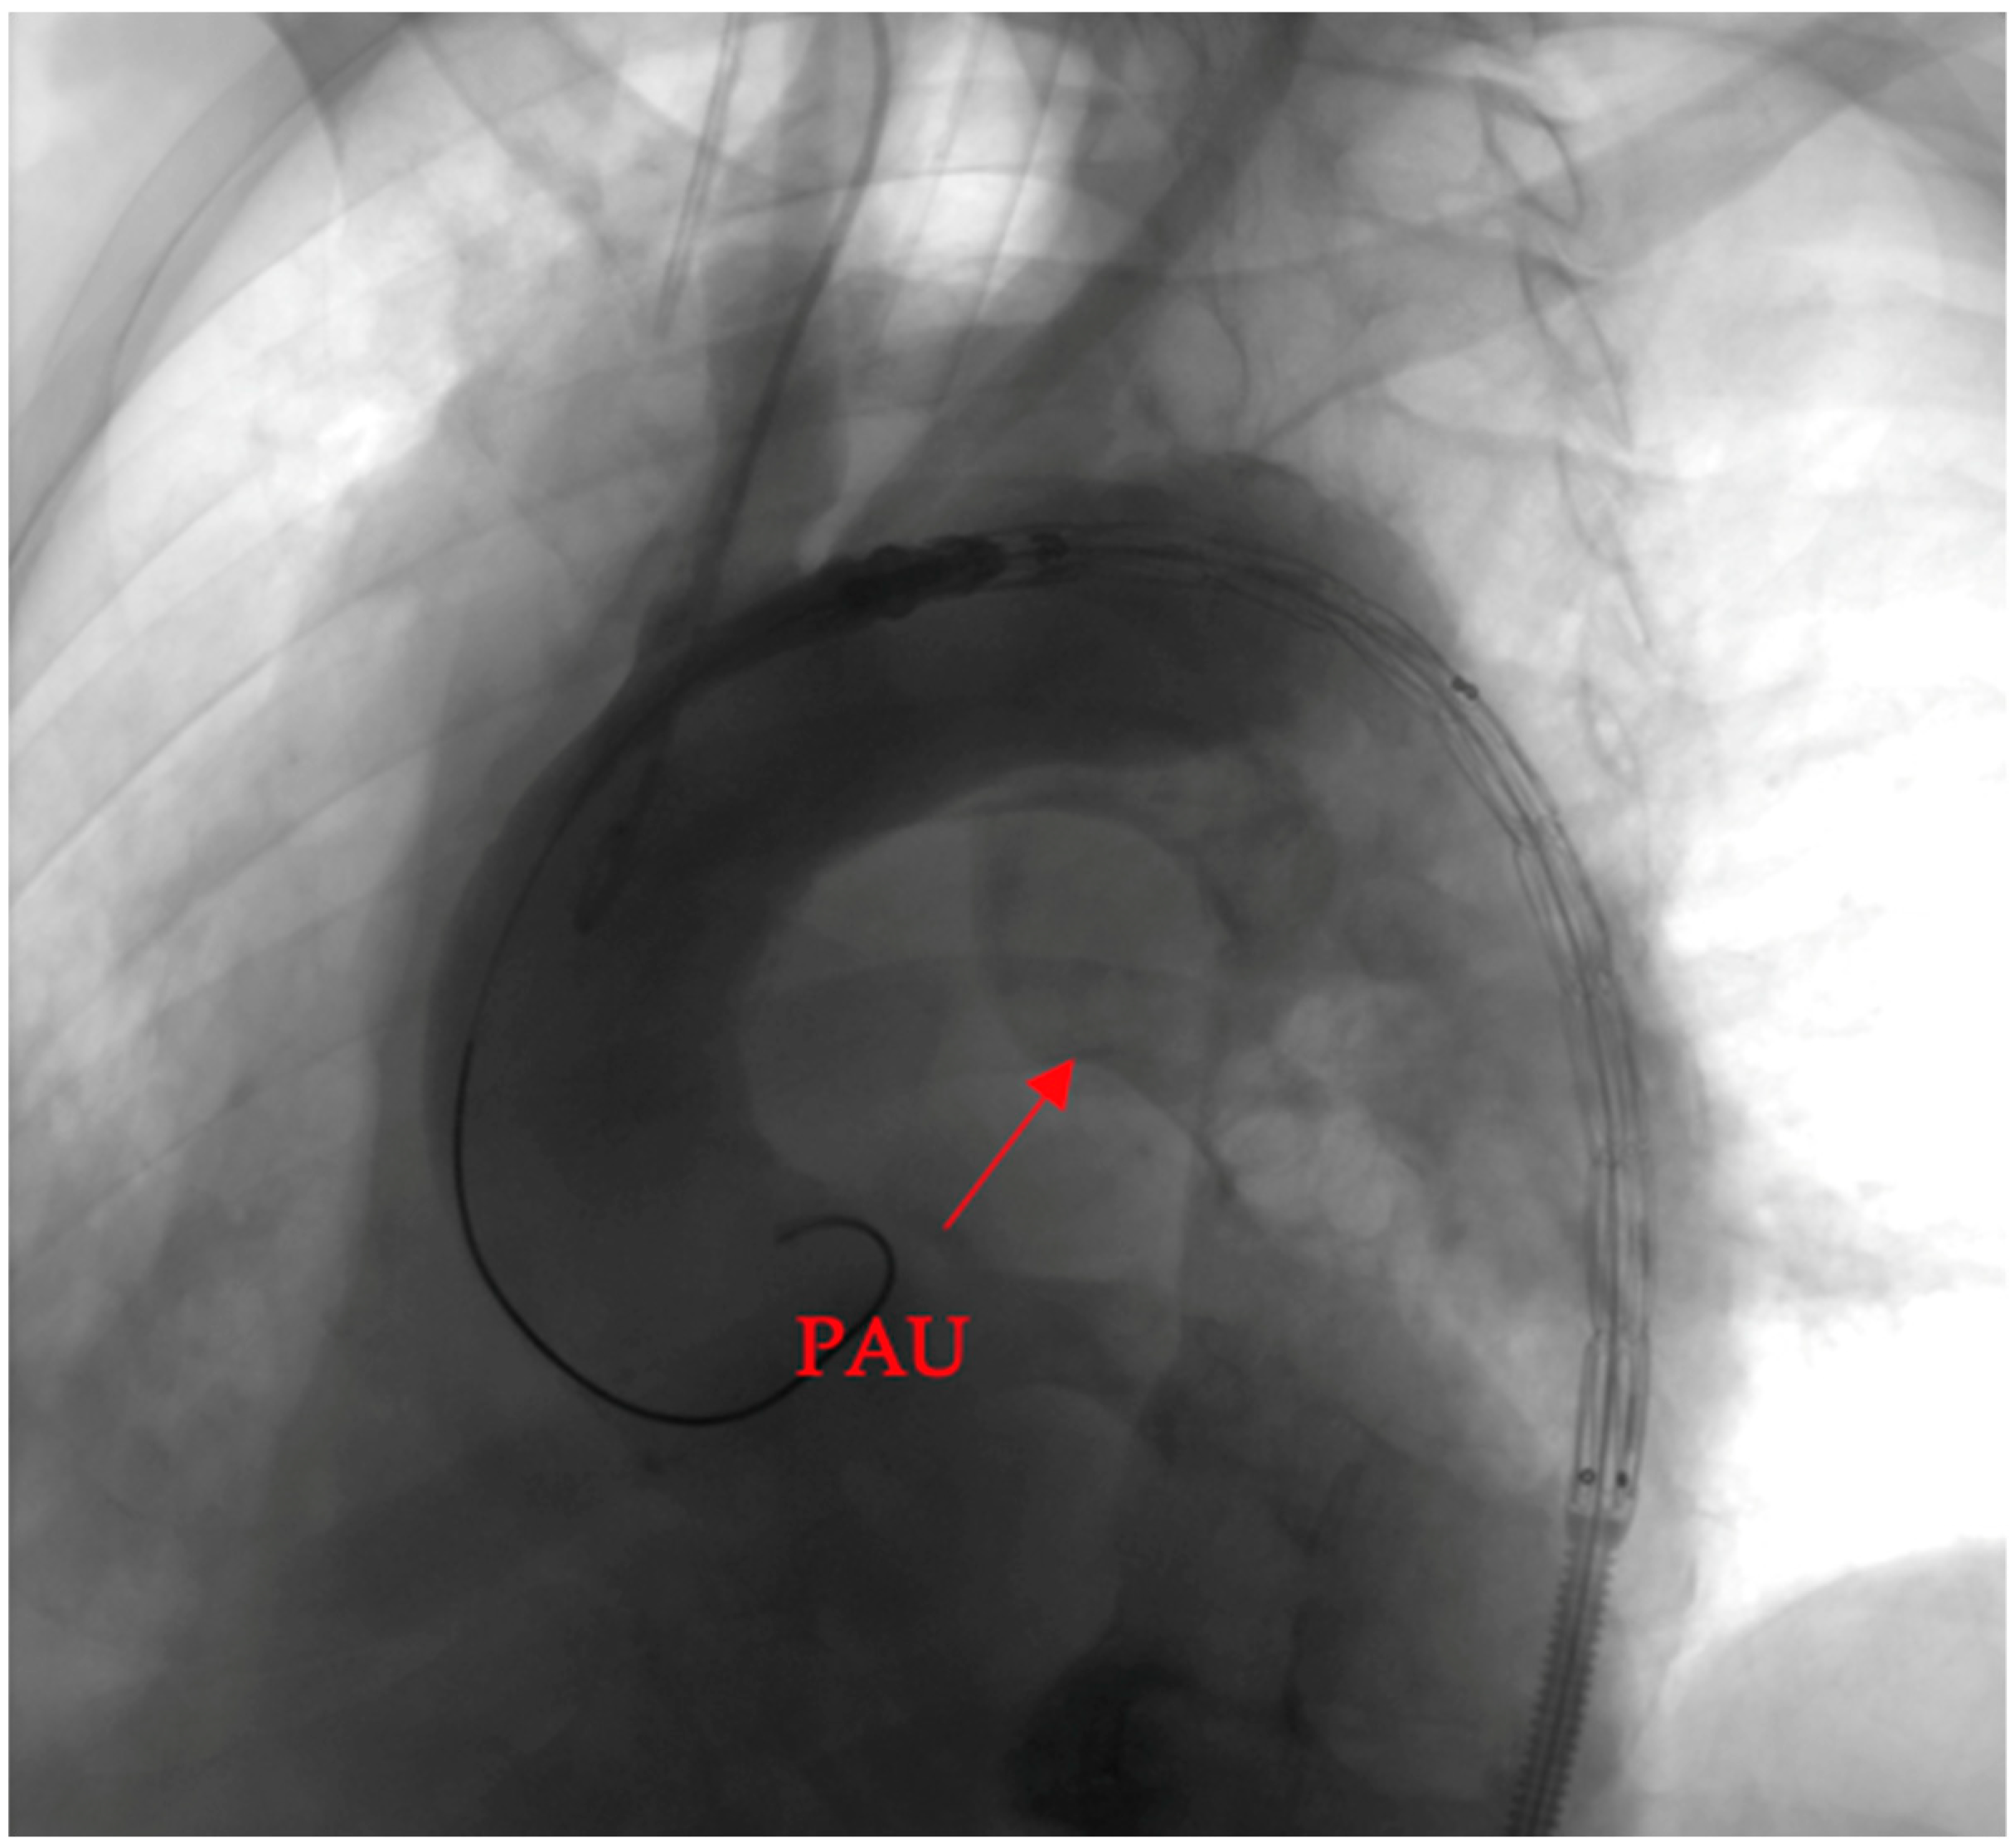

To elucidate the efficacy of the deployed covered stent graft in addressing the penetrating aortic ulcer (PAU), we present a visual narrative captured through contrast-enhanced imaging.

Pre-intervention assessment (Figure 4).

Figure 4.

Pre-intervention assessment.

The initial image provides a snapshot of the aortic landscape before the intervention. Contrast material was injected to illuminate the vascular architecture, allowing for a detailed assessment of the PAU. The image showcases the breach in the aortic wall, offering a visual testament to the complexity of the lesion.